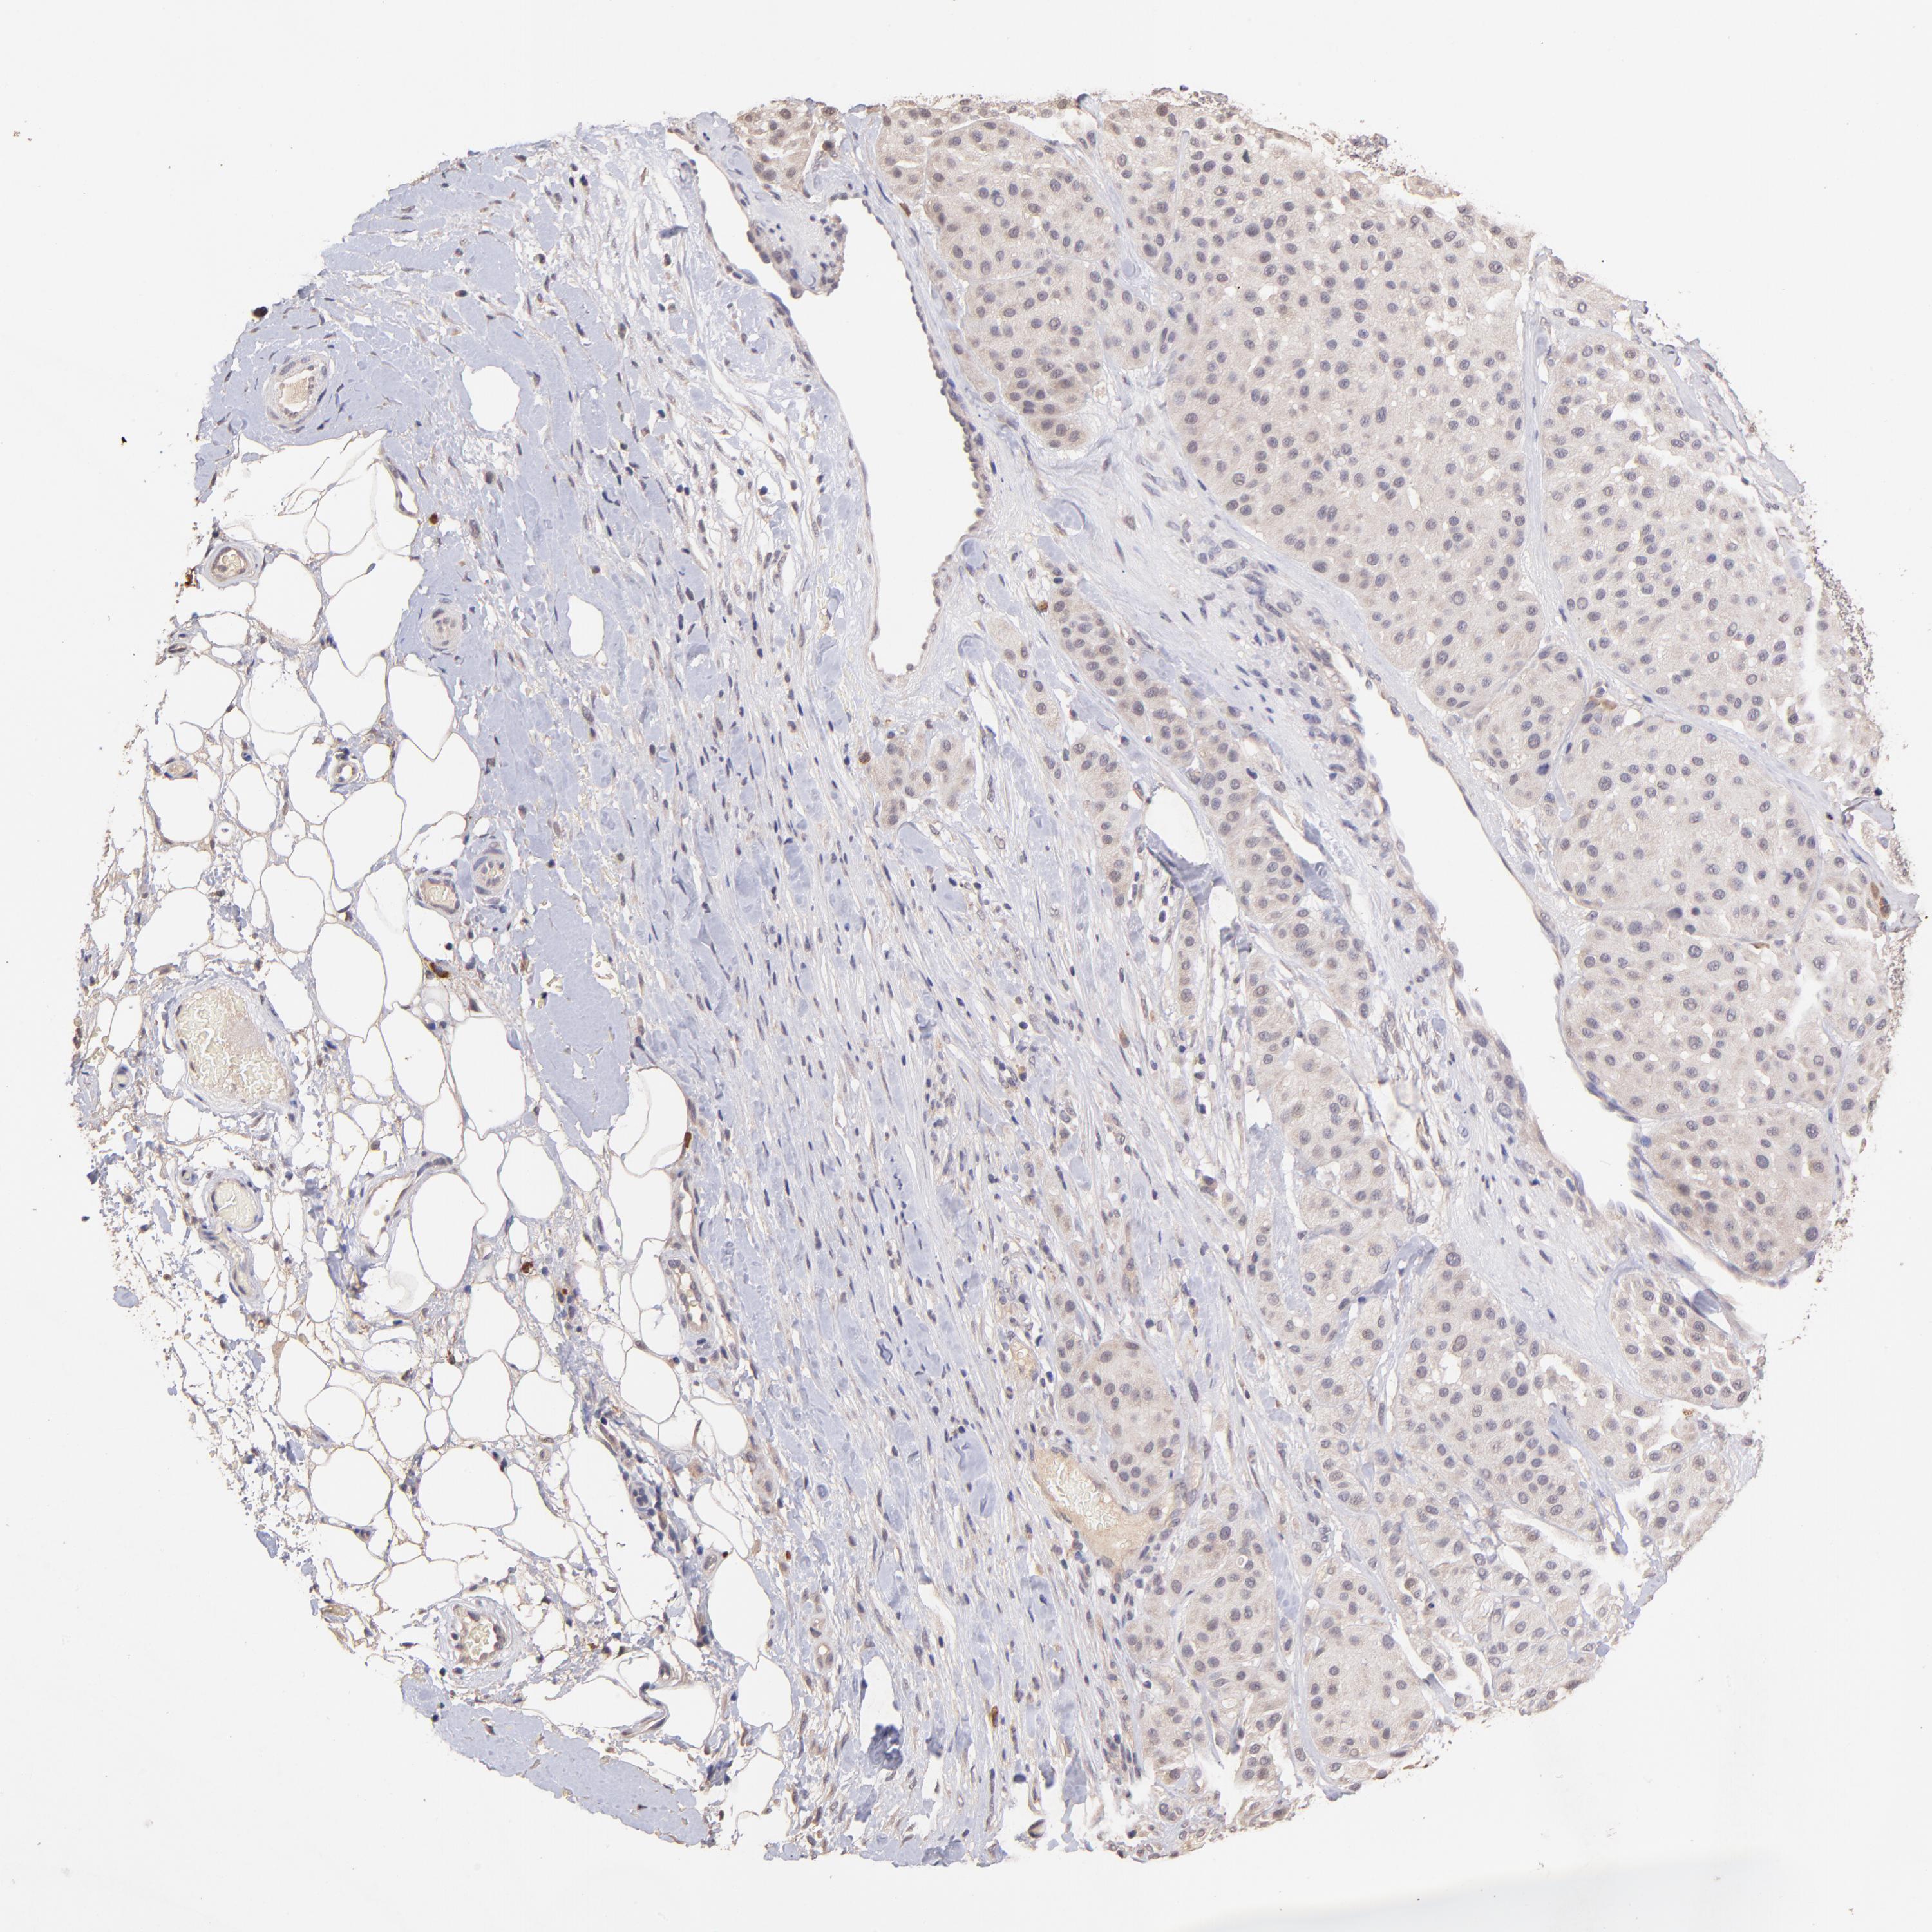

MELANOMA - Protein expressioni

A mouse-over function shows sample information and annotation data. Click on an image to view it in a full screen mode. Samples can be filtered based on level of antibody staining by selecting one or several of the following categories: high, medium, low and not detected. The assay and annotation is described here.

Note that samples used for immunohistochemistry by the Human Protein Atlas do not correspond to samples in the TCGA dataset.

Antibody stainingi

Antibody staining in the annotated cell types in the current human tissue is reported as not detected, low, medium, or high, based on conventional immunohistochemistry profiling in selected tissues. This score is based on the combination of the staining intensity and fraction of stained cells.

Each image is clickable and will lead to virtual microscopy that enables deeper exploration of all samples and also displays staining intensity scores, fraction scores and subcellular localization as well as patient and tissue information for each sample.

Antibody HPA002633

Antibody HPA046758

Antibody CAB010906

Staining

High

Medium

Low

Not detected

Intensity

Strong

Moderate

Weak

Negative

Quantity

>75%

75%-25%

<25%

None

Location

Nuclear

Cytoplasmic/membranous

Cytoplasmic/membranous,nuclear

Malignant melanoma, NOS

Malignant melanoma, Metastatic site

Malignant melanoma in situ